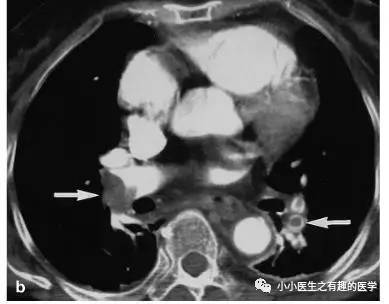

如图,高密度影的那一条。不怕,有增强CT证实。

再来一个图。

仔细看,有端倪。增强CT可以核实。

很明显,病人做了CT平扫,我们要仔细阅片,发现可疑,及时增强CT,要不然就漏诊了。